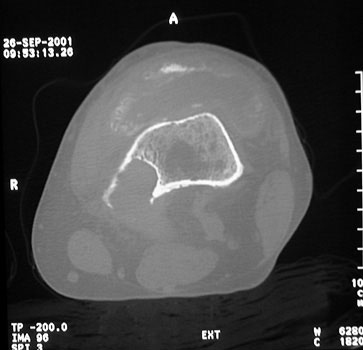

OSTEOLYSIS

Radiograph and CT

CT guided biopsy